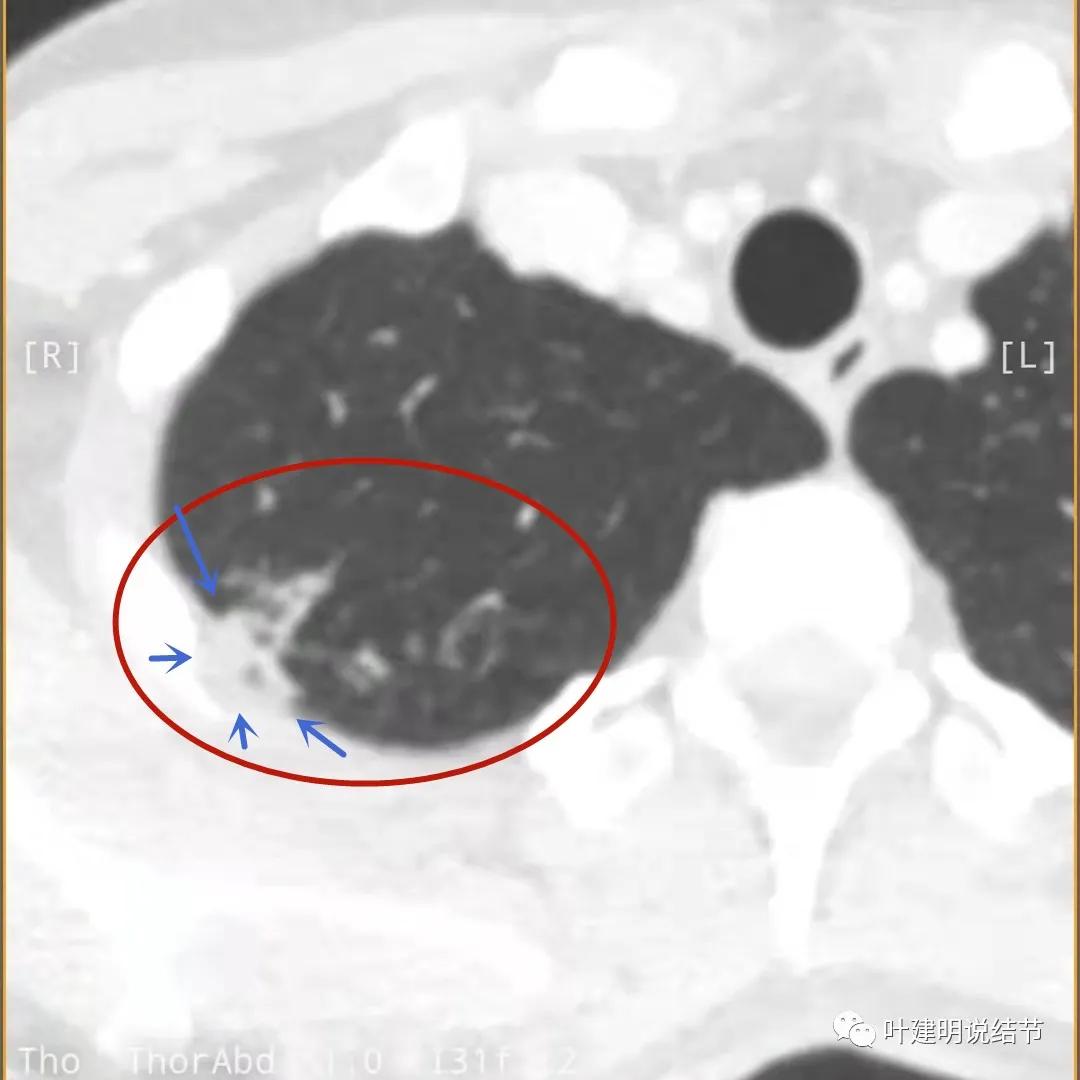

下面是今年复查的平扫片子,来看看有什么变化:

病灶邻近胸膜异常增厚(蓝色箭头)

有卫星灶(绿色箭头),邻近胸膜明显增厚,且模糊,边不清

邻近胸膜增厚

主病灶此层面似三角形,邻近胸膜增厚(蓝色箭头),结节实性部分密度较高(粉色箭头),边缘显模糊(砖色箭头)